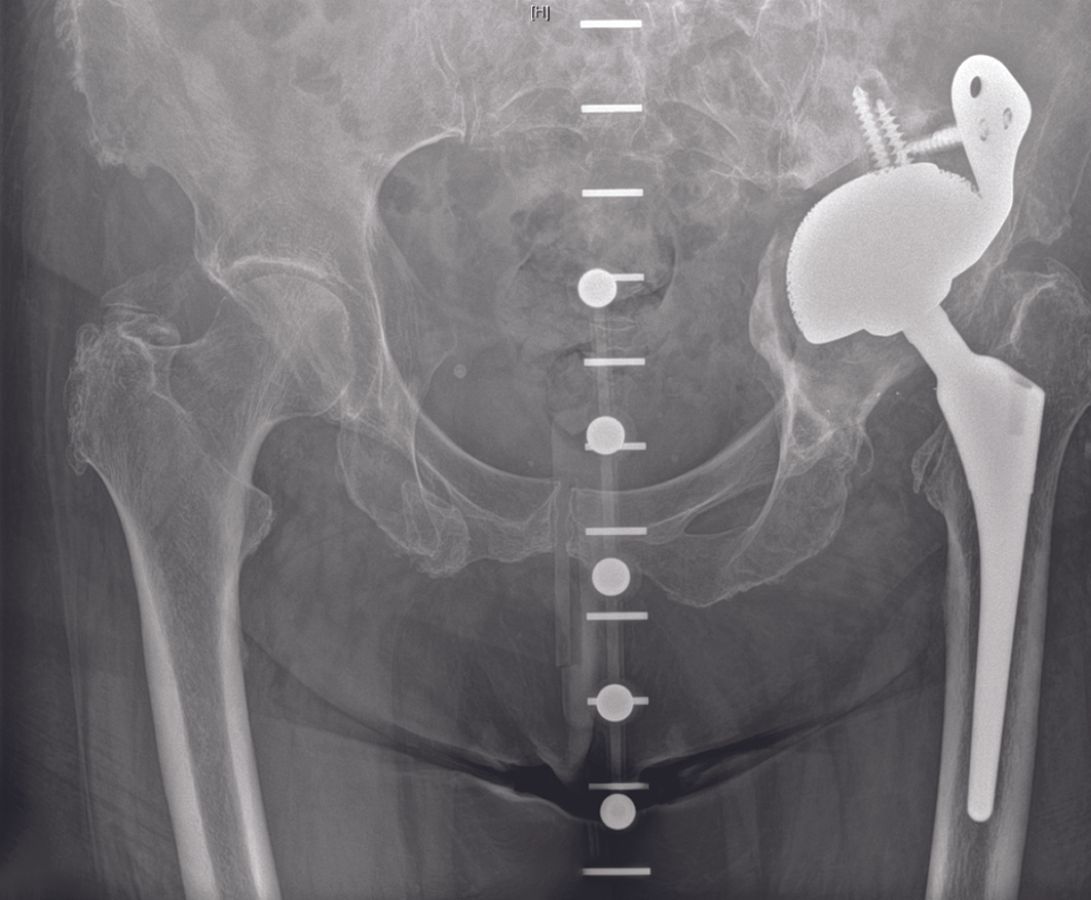

Preoperative radiological assessment with plain radiographs and CT is commonly performed (Fig. 1).

With the patient in lateral decubitus position, an anterolateral or posterior approach to the hip is performed dependent on the approach that had been previously used (Fig. 2).